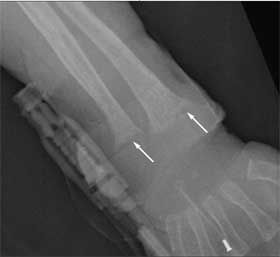

A plain radiograph demonstrated an acute displaced fracture of the left femur (Figure 1). Child Protective Services (CPS) was notified and a skeletal survey was ordered. Images revealed a healing fracture of the right distal radius; an acute linear, nondisplaced fracture of the right parietal skull; and pleural changes associated with fourth and seventh left rib fractures. Also evident were cupping and fraying of the metaphyses of the long bones and demineralized bone density (Figure 2). Results of an ophthalmological examination were normal. An MRI scan of the brain revealed the skull fracture but otherwise showed normal findings.